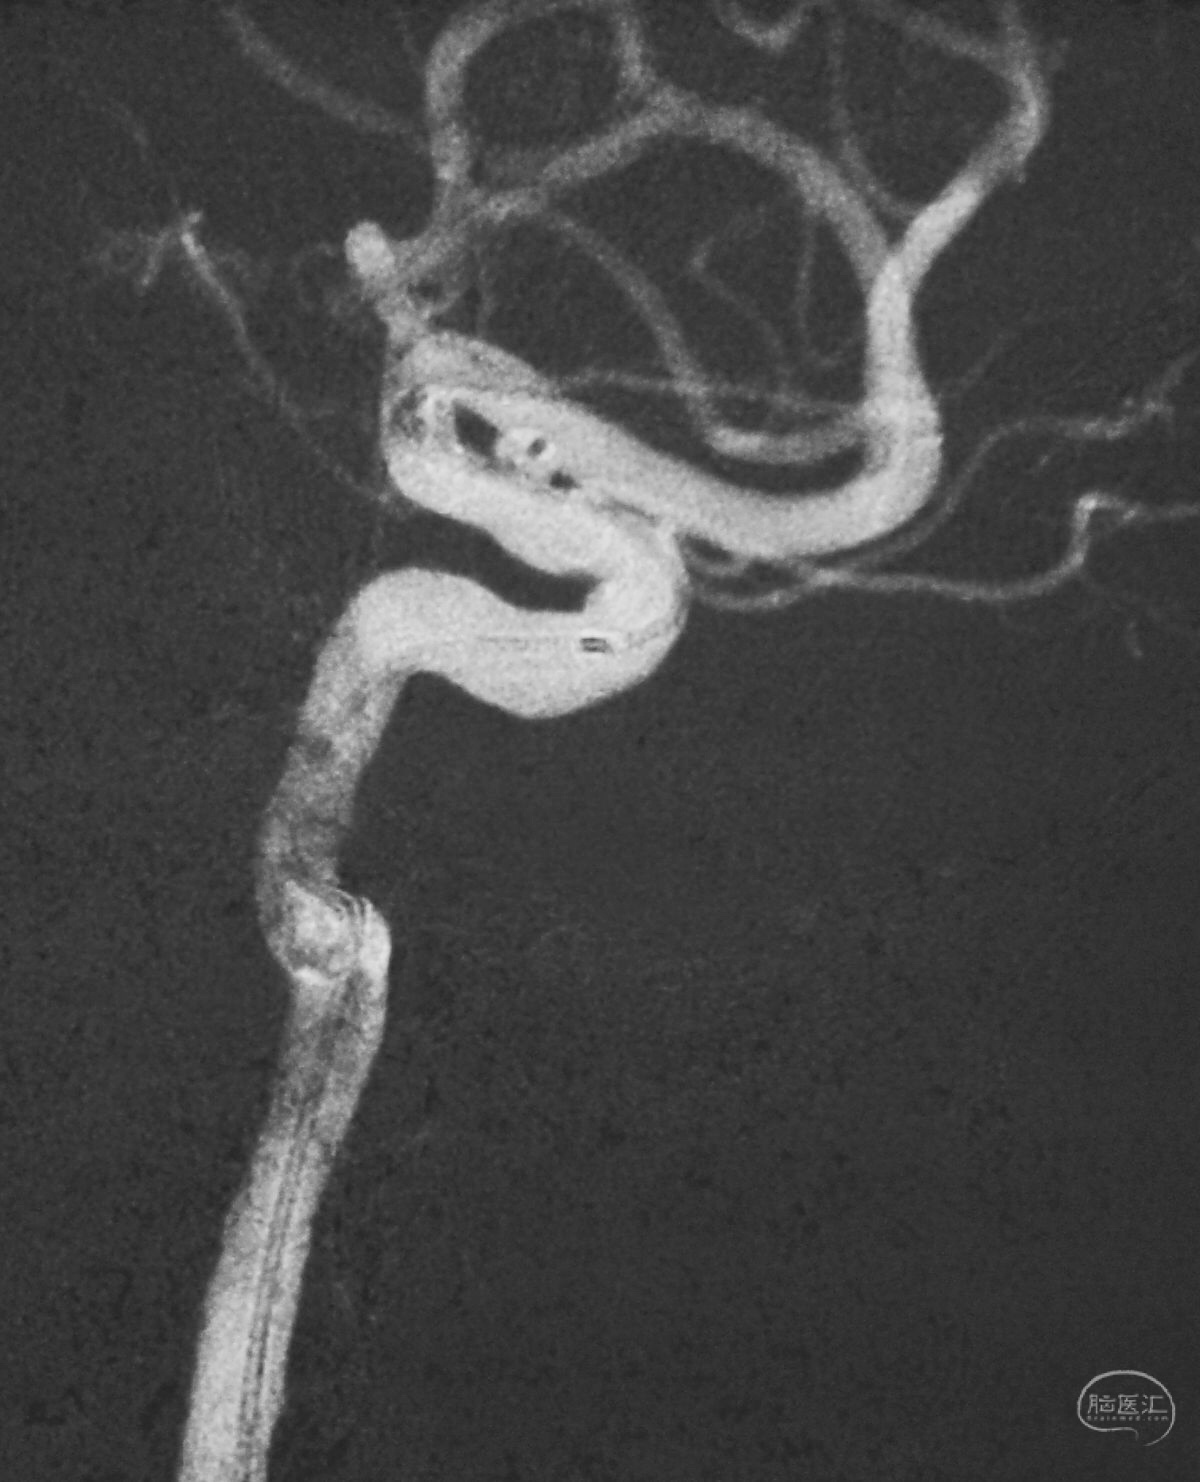

术后右椎动脉工作位造影,

以及正位造影显示动脉瘤完全栓塞,载瘤动脉畅通。

解脱第一枚Solitaire 4×20支架后,套叠置入第二枚Solitaire 4×20支架,置入两枚支架的原因是考虑该瘤是夹层动脉瘤,多支架能够强化血流导向作用,有利于夹层愈合。